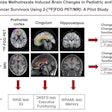

Chinese researchers from Fudan University in Shanghai used a 3D deep convolutional neural network to extract deep metabolic imaging indices from F-18 FDG-PET scans. The model effectively differentiated between Parkinson's disease and other parkinsonian syndromes, such as multiple system atrophy and progressive supranuclear palsy, according to findings.

In this study, the researchers built a 3D deep convolutional neural network, known as the Parkinsonism Differential Diagnosis Network (PDD-Net), to automatically identify imaging-related indices that could support the differential diagnosis of parkinsonian diseases. This model was used to examine parkinsonian PET imaging from two groups: more than 2,100 patients from China and 90 patients from Germany.